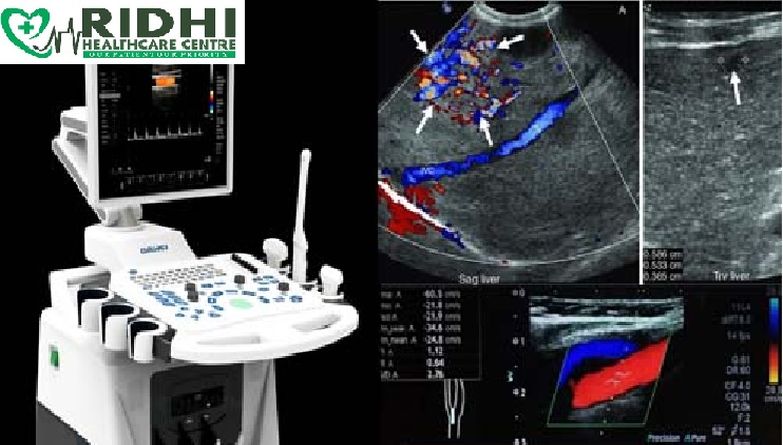

Color Doppler services refer to medical imaging procedures that use a technique called color Doppler ultrasound to visualize and assess blood flow within the body.